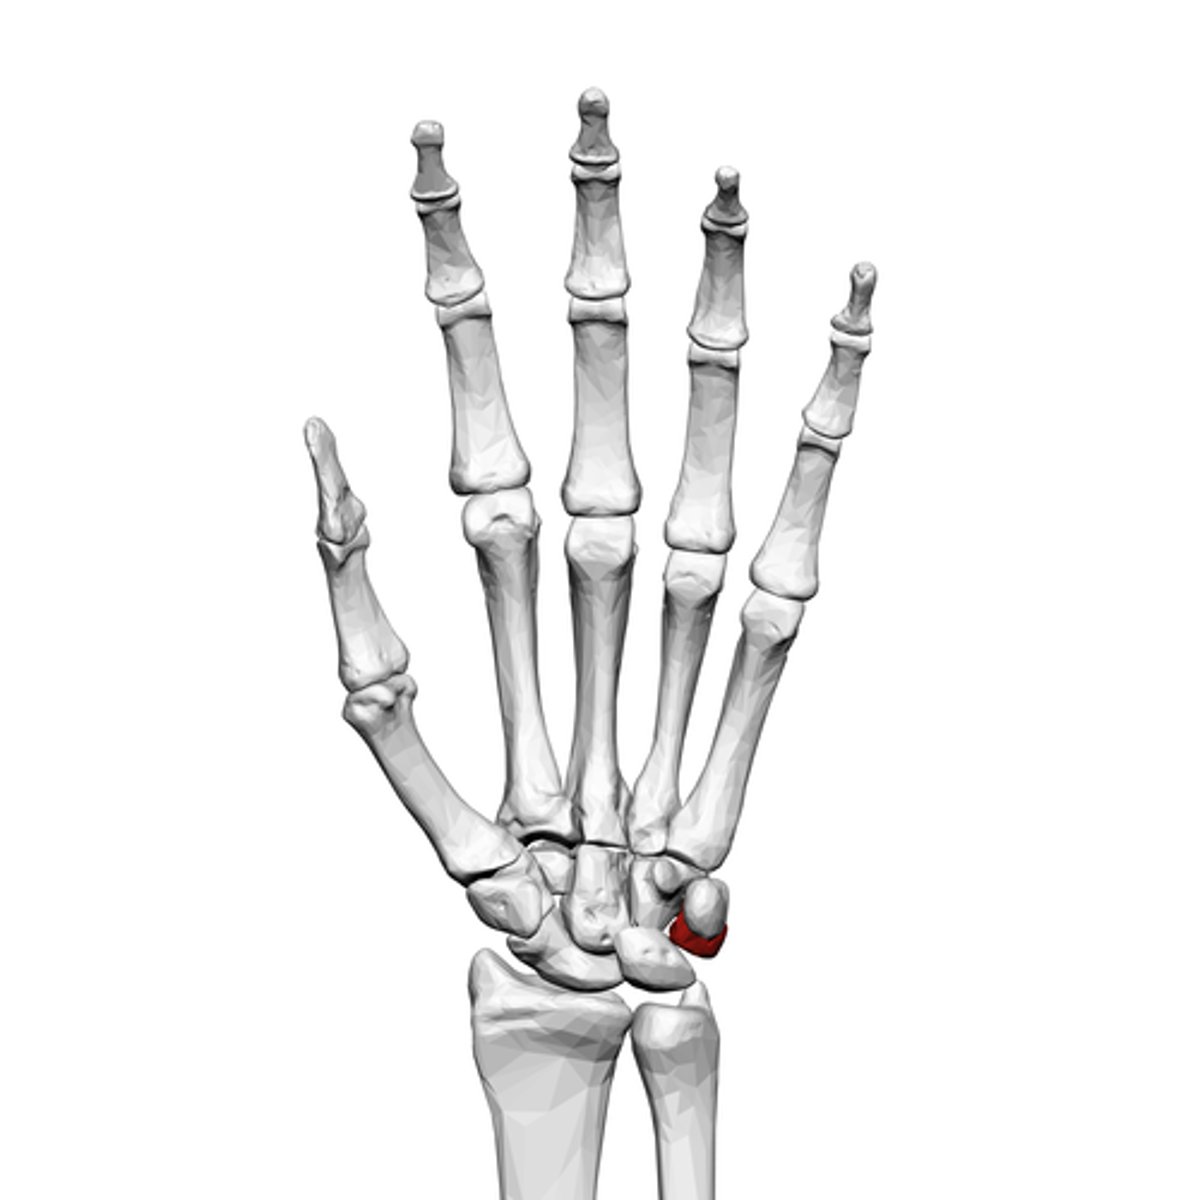

What is the term of the bones highlighted in red?

Pisiform